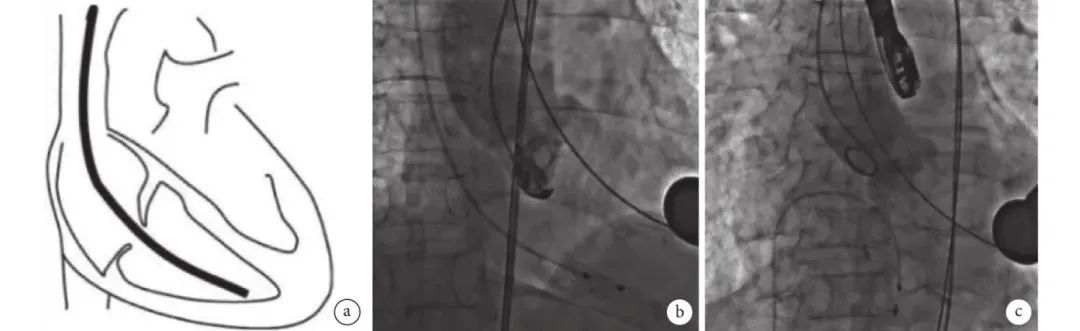

经股静脉或颈静脉穿刺鞘管置入右室临时起搏电极,电极尖端一般位于右室心尖部或室间隔(图3),置入过程操作轻柔,全程避免导线张力过高,以免造成右室穿孔[12]。起搏电极到位后,须测试并确保其稳定工作。因TA-TAVR传导阻滞发生率相对较低,对于传导阻滞发生低危患者,即术前无完全性右束支传导阻滞,瓣膜植入后心电图无变化,可术毕拔除起搏导线,有利于患者尽早下床活动;如术前评估患者传导阻滞发生率较高,即术前心电图提示完全性右束支传导阻滞,或术中出现QRS波变宽,完全性左束支传导阻滞[13-14],则可选择保留经颈静脉心内膜临时起搏电极,或瓣膜植入后心尖缝合心外膜临时起搏电极,术毕保留起搏导线的同时不影响患者下床活动,利于术后康复。

图片

图3 临时起搏电极置入

(a:穿刺鞘管置入右心室临时起搏电极;b:经股静脉;c:颈静脉)